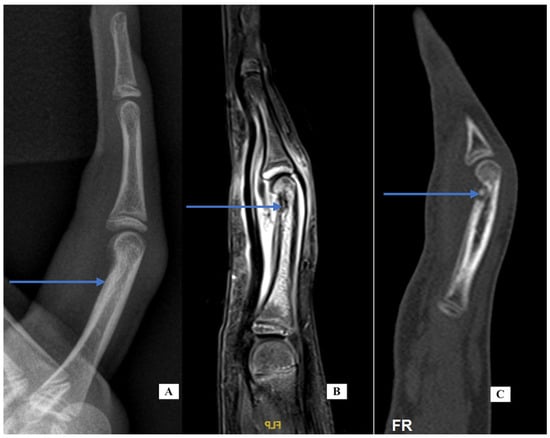

Case 5: A 67-year-old male right-handed attorney presented with a 3-week history of left ring finger swelling of the PIP joint. He was seen elsewhere and started on both colchicine and cephalosporin without improvement. His history was significant for a fracture of the same finger as a child, a laceration of the same finger years prior and an infection 8 months before his visit, also of the same finger, that was treated with oral antibiotics and thought to have resulted from a presumed “bug bite”. He had a history of prostate cancer treated by brachytherapy. The exam was notable for moderate diffuse swelling around the PIP joint and a limited motion arc of only 5 degrees. There was no tenderness along the flexor sheath. There was mild volar and dorsal erythema. His labs were notable for mildly elevated CRP (1.4), ESR (2), and white blood cell (WBC) (14). An aspiration was performed under digital block to rule out infection and was culture negative. His X-rays (Figure 4, PA and lateral views, left and center) show angulation from the old injury and advanced PIP arthritis. CT scans for gout protocol were performed in dual-energy mode. (SOMATOM Definition Force, Siemens Medical Systems, Forchheim, Germany, with tube potentials of 80 and 140 kV with an additional tin filter). Post-processing was performed using a commercial software program (Syngo CT Workplace, Siemens Medical Systems, syngo.via VB80E) to create material-selective images, where monosodium urate (MSU) deposits were color-coded as green. A CT scan (Figure 4, right) was performed using the above gout protocol. Volar to the F4 P1 and P2 dual-energy map images demonstrate a focus of urate crystal collection (shown in green), confirming the diagnosis of gout. He was given oral indomethacin with near-immediate improvement in his pain and swelling. The finger PIP joint motion improved to an arc of 35 degrees. He was referred to his family doctor for additional treatment for his gout.

Case-specific comment: Despite the complex history of the digit, the most likely diagnosis was still gout based on his history and examination [1]. A CT scan with gout protocol confirmed the diagnosis.

Figure 4. Case 5—X-ray PA (A) and lateral (B) of the finger; CT scan oblique for gout of the hand (C). Only the green color is significant. Purple represents calcifications.